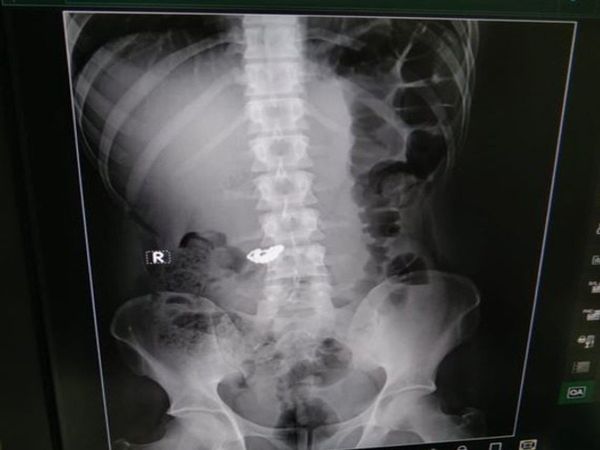

जानकारी के मुताबिक, घटना सिटी मार्केट के पास एमटी रोड की है। बताया जा रहा है कि शनिवार को आरोपी विजय अपने साथी संजय और प्रेम के साथ बाइक पर आया और एक महिला से तीनों ने तकरीबन 7.5 ग्राम सोने की चेन को छीन लिया। चेन छीनने के बाद तीनों भागने की कोशिश कर रहे है। लेकिन, महिला ने चिल्लाना शुरू कर दिया, जिसके बाद वहां मौजूद लोगों ने उन्हें पकड़ लिया और उनके साथ मारपीट भी की। लेकिन, इसी बीच विजय के दोनों साथी वहां से फरार हो गए लेकिन वह पकड़ गया। मारपीट में विजय काफी जख्मी हो गया, जिसके बाद उसे विक्टोरिया हॉस्पिटल में भर्ती कराया गया। डॉक्टर्स जब उसका चेकअप किया और एक्स-रे किया गया तो काफी चौंकाने वाला खुलासा हुआ। रिपोर्ट में पता चला कि विजय ने उस चेन को निगल लिया है।

पुलिस और डॉक्टर्स के सामने जब यह सच्चाई सामने आई तो उसे निकालने का फैसला लिया गया। डॉक्टर्स ने आरोपी को पहले छह केले खिलाए और बाद में कब्ज के लिए उसे एक सिरप भी पिलाया जिससे उसका पेट साफ हो सके। डॉक्टर्स इस मकसद में कामयाब भी हो गए और चेन को बरामद कर लिया गया। फिलहाल, पुलिस ने केस ने दर्ज कर मामले की छानबीन शुरू कर दी है। वहीं, यह मामला पूरे इलाके में चर्चा का विषय बना हुआ है।